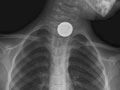

- Find foreign objects, such as coins or

other small pieces of metal, in the tube to the stomach (esophagus), the

airway, or the lungs. A chest X-ray may not be able to see food, nuts, or wood

seen. | A foreign object is seen in

the esophagus, breathing tubes, or lungs. | A tube, catheter, or other